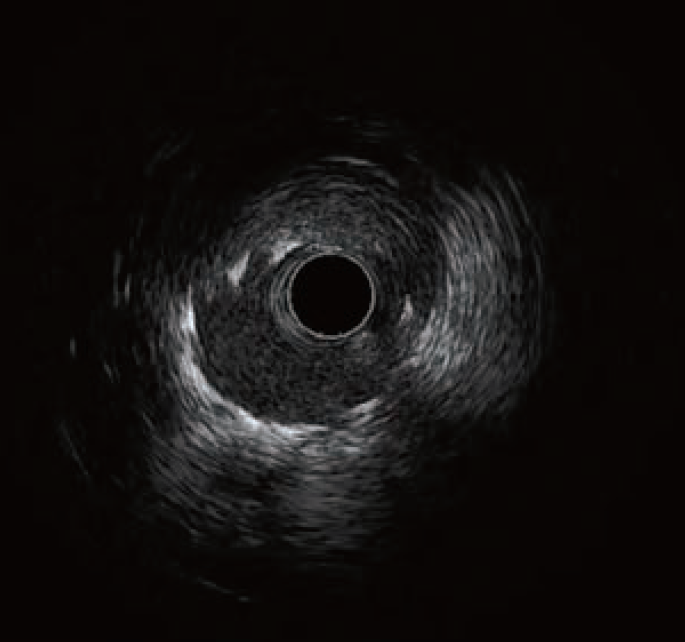

支架膨胀不良

支架膨胀不全识别特点

支架膨胀定义有两种方式:一为测量的支架内最小横断面积的绝对值(ULTIMATE研究结果MSA≥5mm2)。

或者最小支架内面积与预设的参考面积的比值,而这一预设面积可以为支架近端、远端、最大的或平均的参考面积(ULTIMATE 研究结果MSA≥远端参考管腔面积的90%)。

总体来说,支架膨胀越好,长期通畅率越高,支架失败风险越低,患者的临床预后越好,且最小支架内面积的绝对数值相比对比值对于长期支架通畅性的预测价值更好。